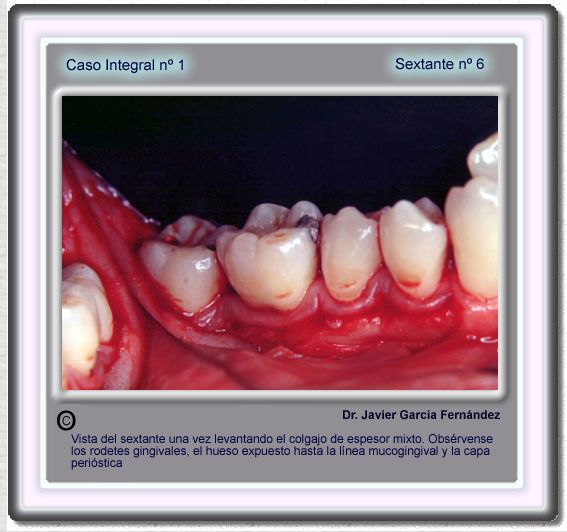

image 99